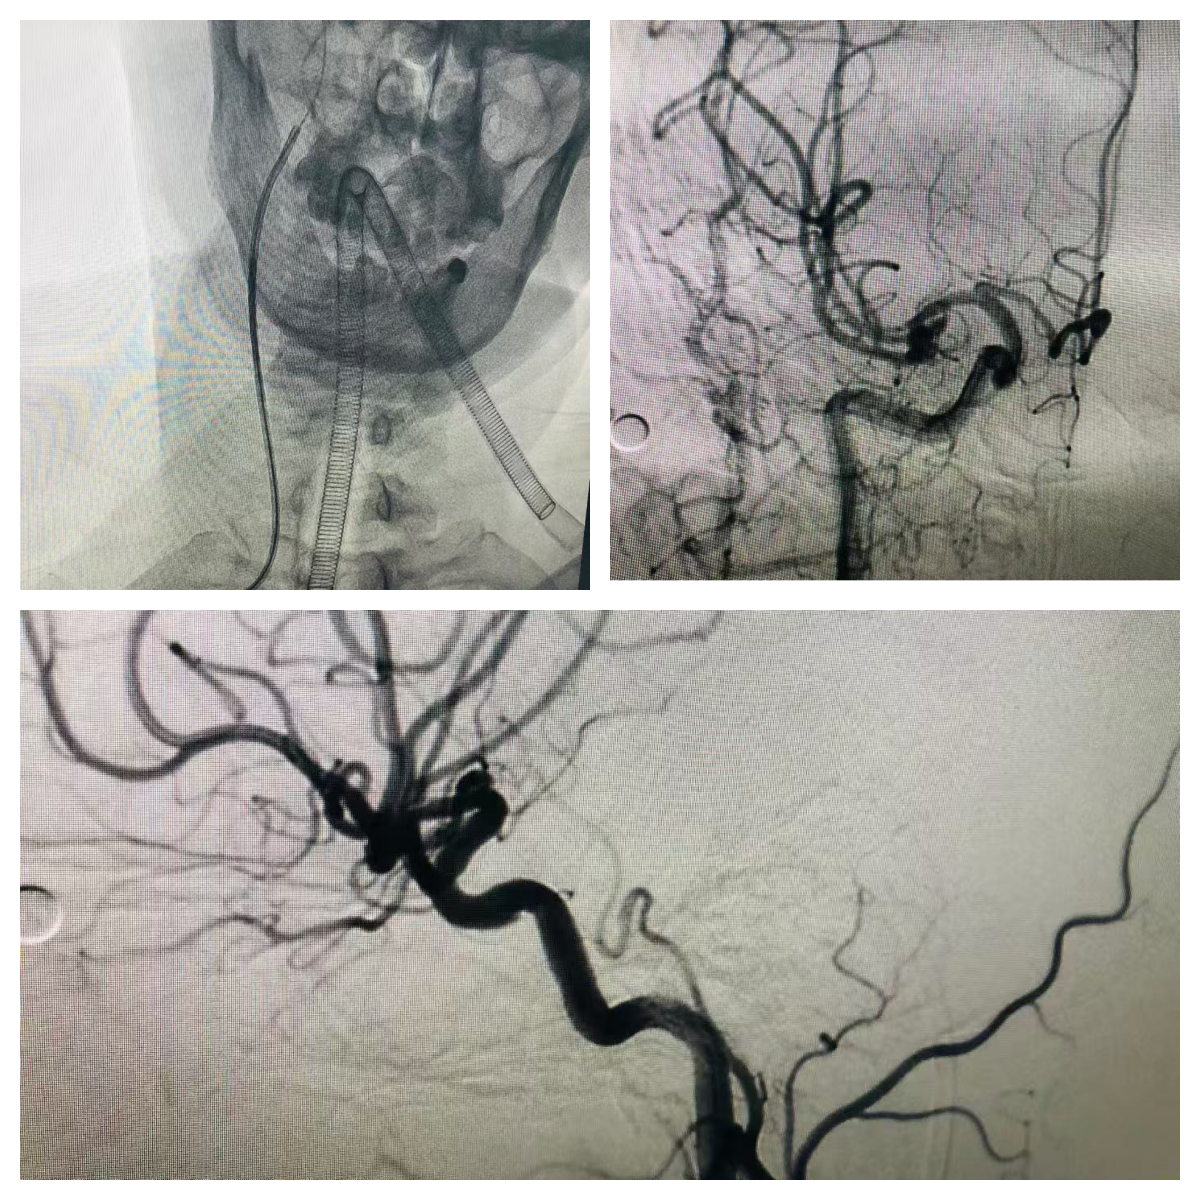

微创精准诊疗新突破——我院神经内科开展经桡动脉行脑血管介入术

脑血管疾病是威胁人类健康的“头号杀手”,其高发病率、高致残率让精准诊断成为诊疗关键。近日,我院神经内科文学主任团队正式启动“经桡动脉全脑血管造影术”新项目,以微创技术革新为阳江地区脑血管疾病患者带来更安全、舒适的诊疗新选择,标志着我院脑血管介入诊疗水平迈入精准微创新时代。

此次我院引进的经桡动脉行脑血管介入术,实现了脑血管介入诊疗的“微创革命”。该技术通过手腕部的桡动脉穿刺建立介入通道,仅需2-3毫米的微小创口即可完成经桡动脉行脑血管介入手术。桡动脉位置表浅、易于压迫,且周围无重要神经和血管毗邻,从根源上降低了血管损伤风险。更重要的是,术后无需长时间卧床,患者穿刺完成后即可下床活动,当天就能正常进食、行走,大幅提升了就医舒适度,也减少了家属的陪护压力。

技术的精准实施离不开强大的硬件支撑与团队保障。我院已配备先进的数字减影血管造影(DSA)系统,其高清晰度成像功能可实时显示颅内颈内动脉、椎动脉、大脑前动脉、大脑中动脉等各级血管的解剖结构,精准捕捉血管狭窄、畸形、动脉瘤等病变细节,为诊断提供“火眼金睛”般的影像支持。同时,科室配备了全套专用介入器械,包括桡动脉穿刺针、造影导管、导丝及术后压迫止血装置等,确保每一步操作规范精准。